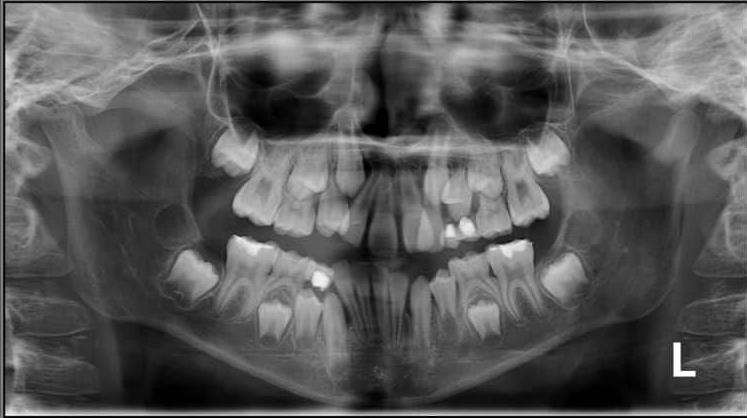

4. How old is the patient with the following X ray?